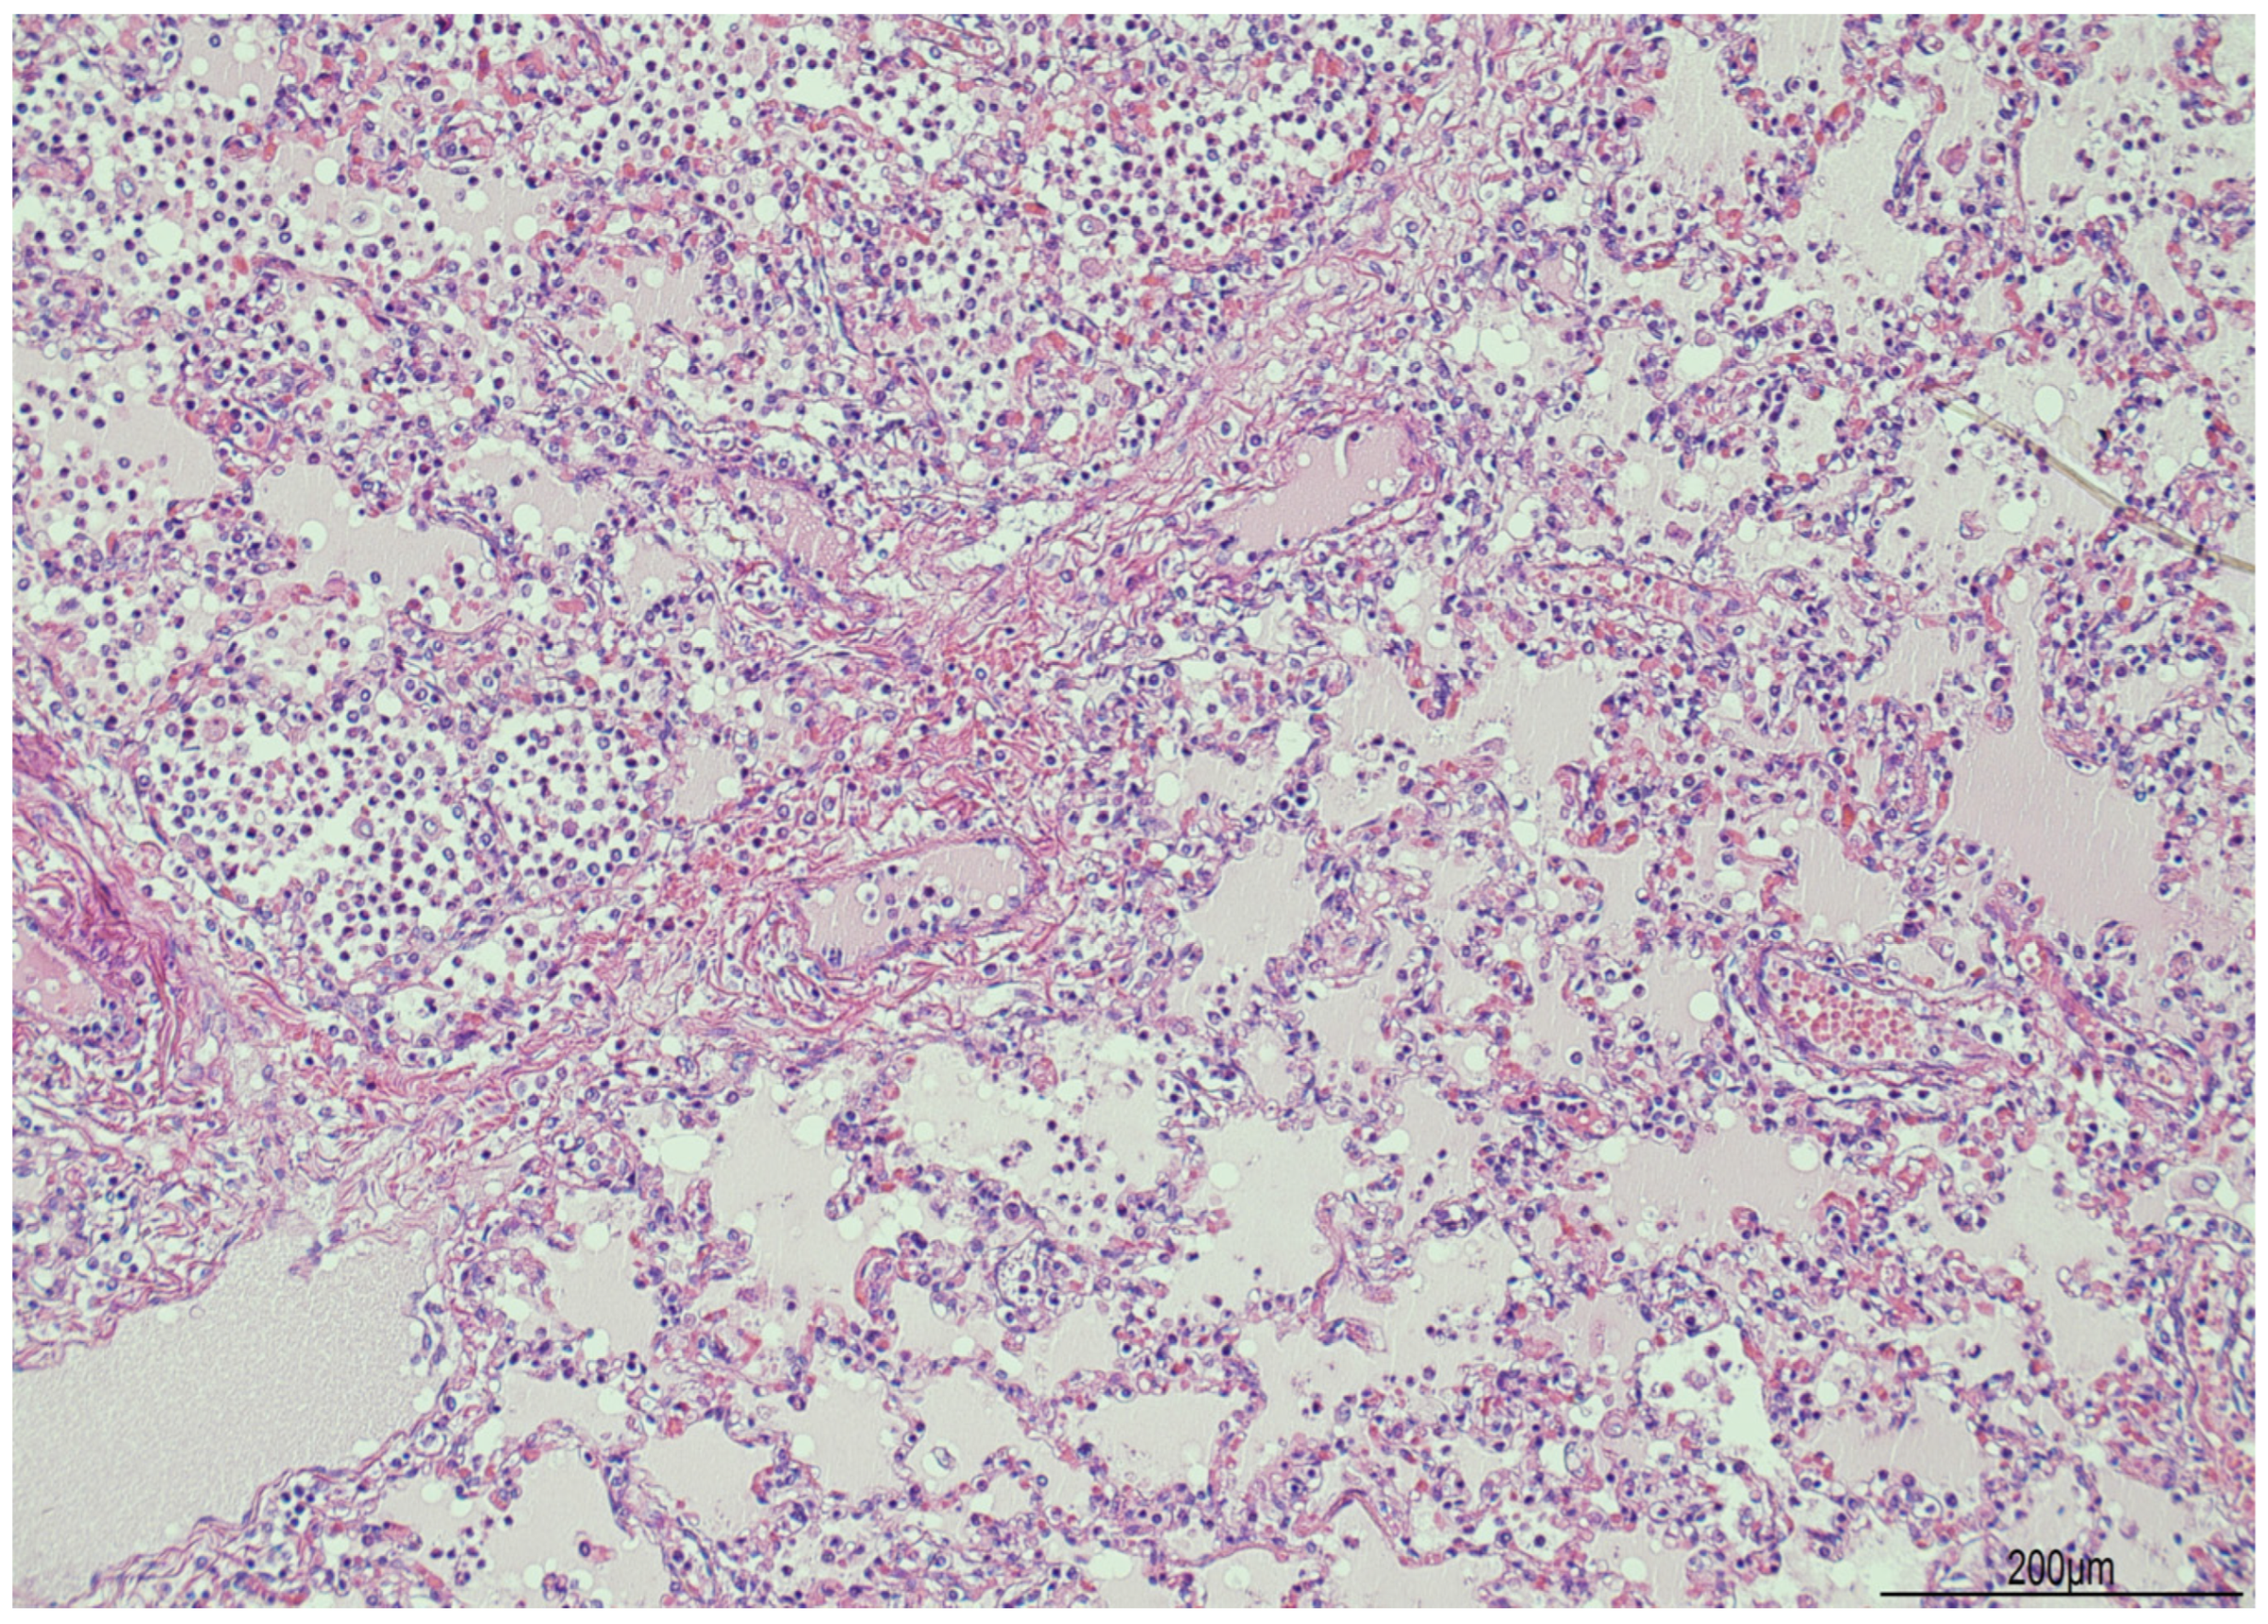

2.2. Autopsy Findings

2.3. Histological Findings